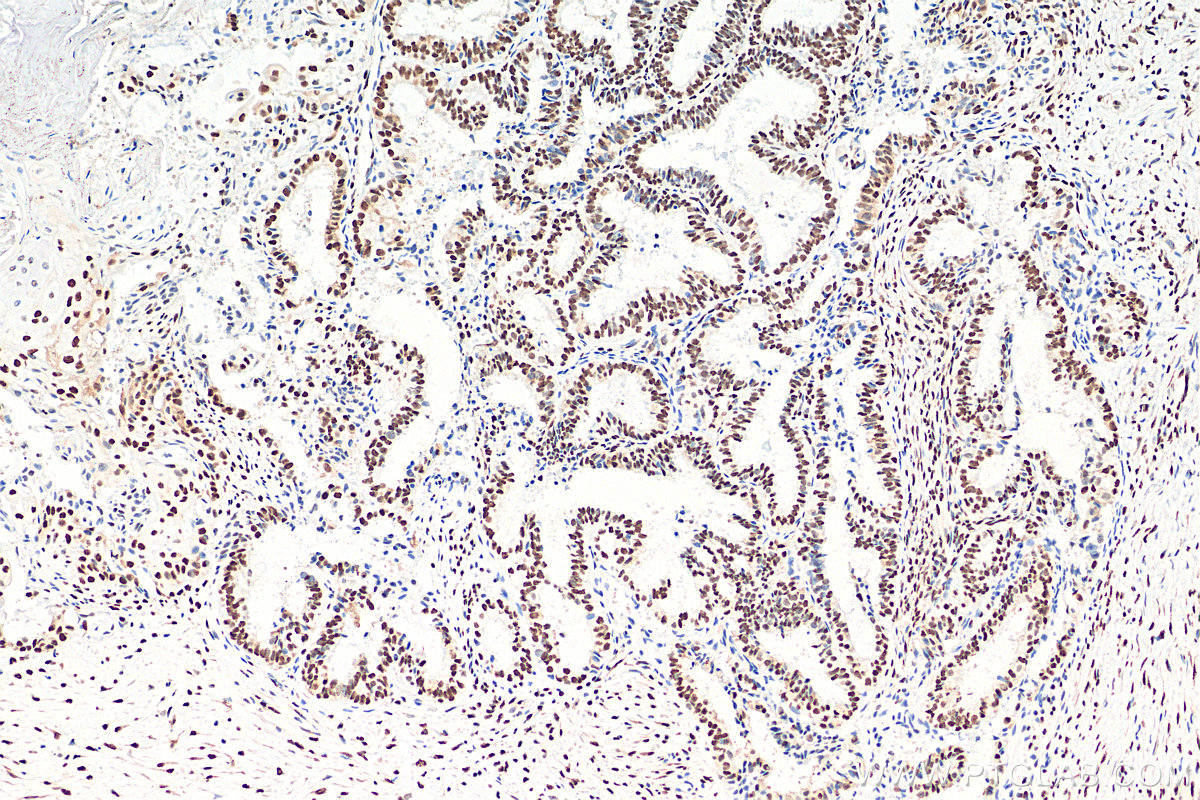

| Positive IHC detected in | rat brain tissue, human ovary tumor tissue, human colon tissue, mouse brain tissue, mouse cerebellum tissue Note: suggested antigen retrieval with TE buffer pH 9.0; (*) Alternatively, antigen retrieval may be performed with citrate buffer pH 6.0 |

| Immunohistochemistry (IHC) | IHC : 1:5000-1:20000 |